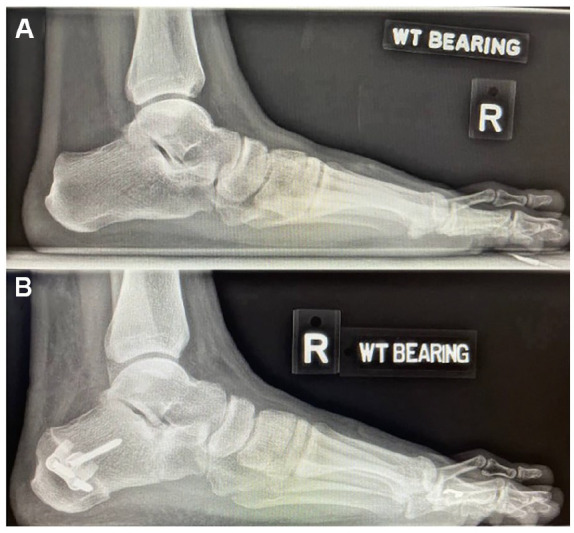

Methods: This retrospective study reviewed 38 patients who underwent LCL for PCFD at a tertiary institution from 2012 to 2022. Patients were divided into 2 groups: the 25 who received autografts (group A), and the 13 who received allografts (group B) mixed with BMAC. Clinical outcomes were assessed using visual analog scale (VAS), American Orthopaedic Foot & Ankle Society (AOFAS) ankle-hindfoot scores, and 36-Item Short Form Health Survey (SF-36) scores at 6 and 24 months postoperatively. Radiologic union was evaluated through serial weightbearing radiographs at regular interval post-surgery.